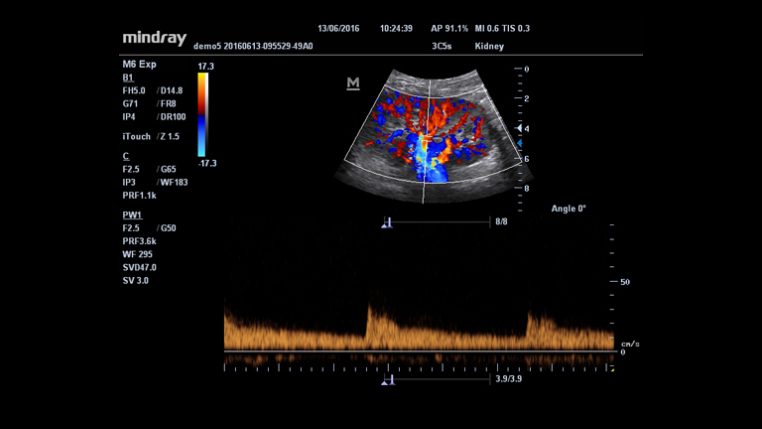

HR Flow?

iTouch?? (Optimización de Autoimagen)

Obtenga una optimización de autoimagen instantánea en Modos B, Color y PW haciendo clic en una sola tecla.